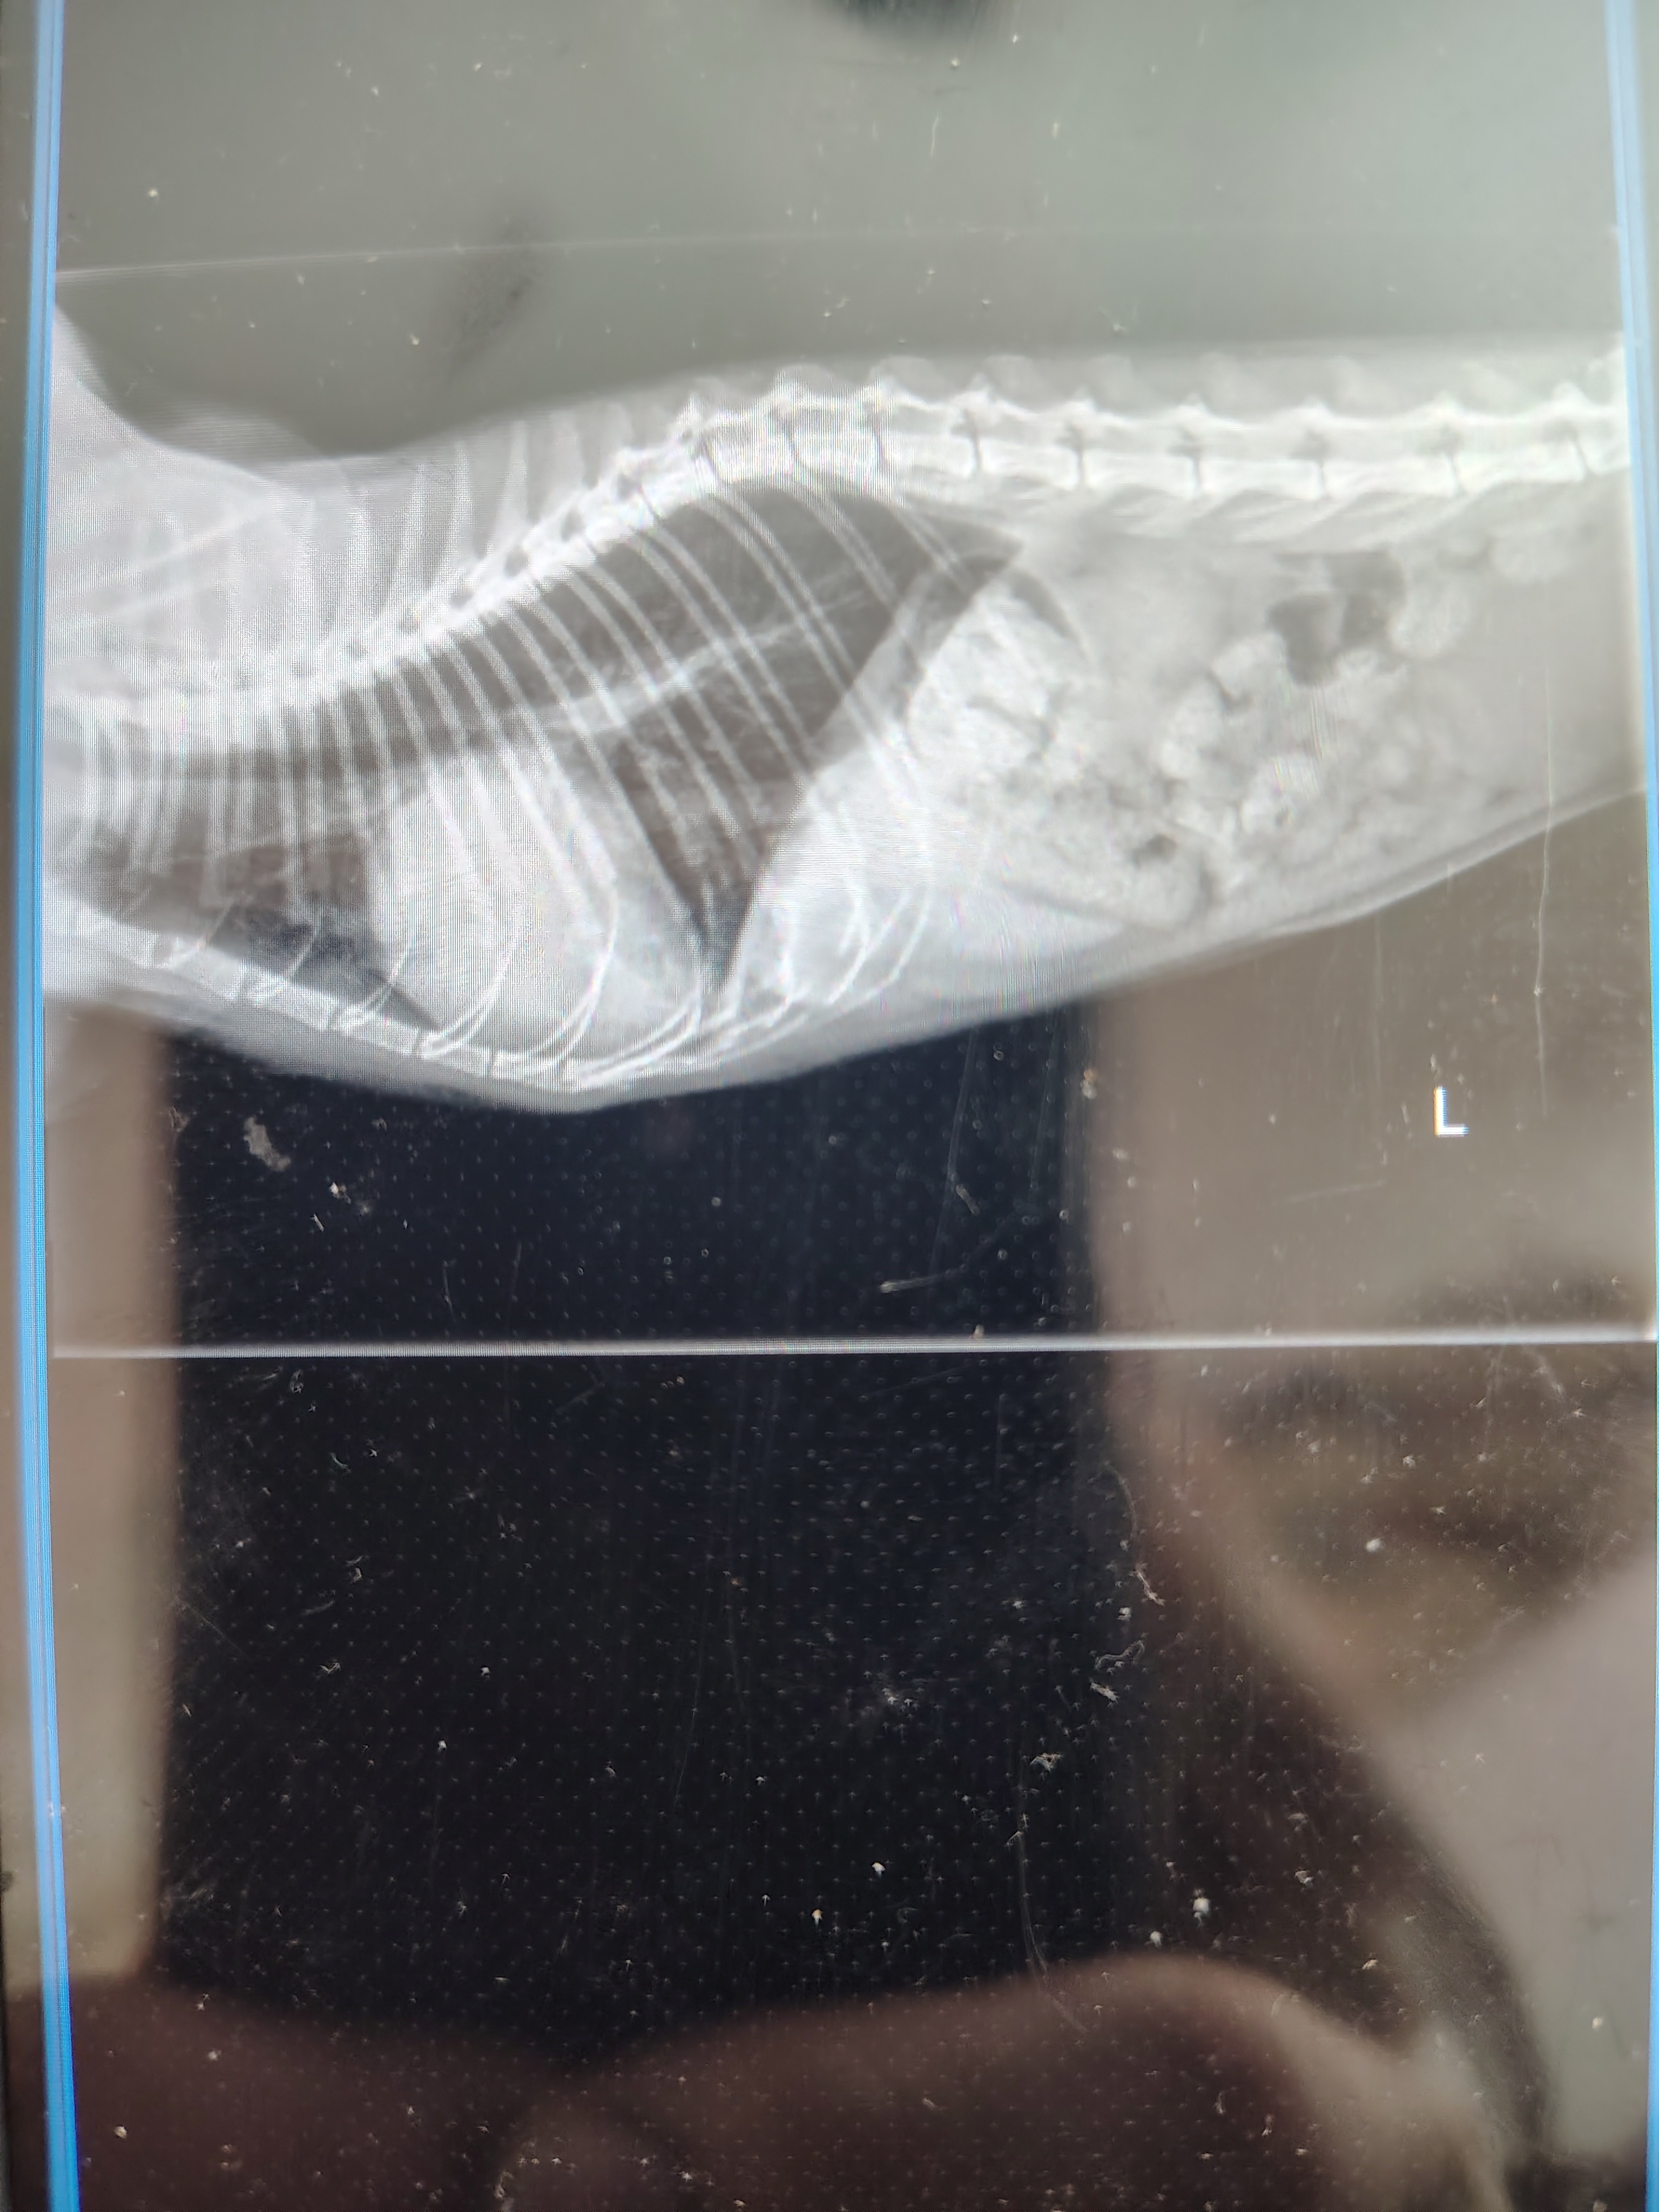

They performed X-rays and suspect that Hypertrophic Cardiomyopathy (HCM) may be the cause, but they can’t say for certain yet. Because Mijo’s breathing was so irregular, they weren’t able to safely complete a heart ultrasound. For now, he’s been started on medication for HCM and we were told to come back in a month. (f he’s strong enough to make it that long.)

Our vet also recommended additional testing to figure out what’s really going on, including blood work to rule out thyroid issues and a heart ultrasound once he’s stable. Without these tests, we’re left guessing and hoping the medication he’s on is the right one.

Like many people right now, the cost is overwhelming. So far the X-ray and exam have been $450, the blood test is $200, and the heart ultrasound will be $650. We just want answers so we can give Mijo the right treatment and the best chance to recover.